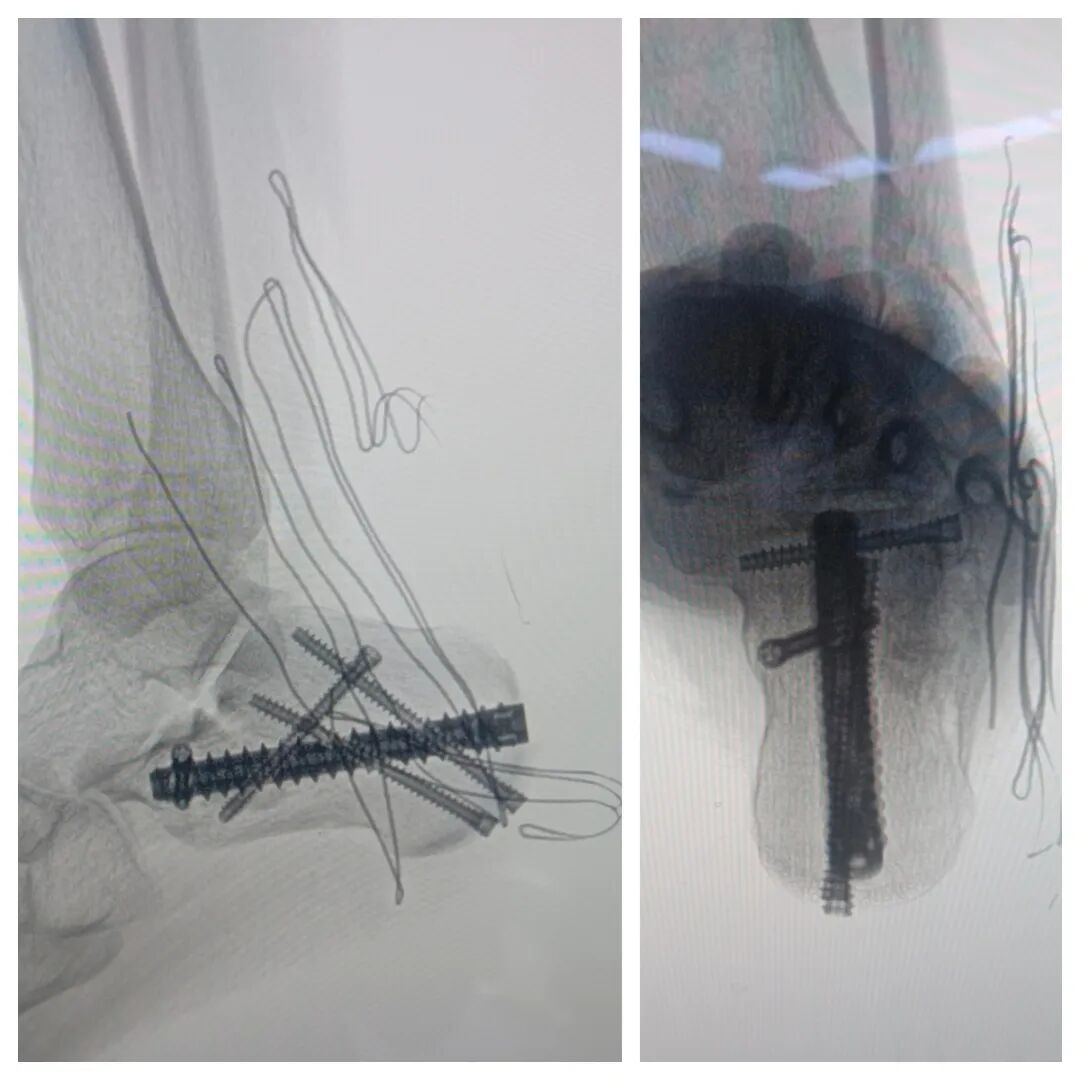

近日,一名14岁的患者因跟骨骨折,来河南大学淮河医院就诊,创伤骨科郭建阔主任团队接诊后,没有选择传统的“大刀口”,而是为患者实施“跗骨窦入路+跟骨钉中钉”的微创方案。

主切口仅3厘米;

系开封地区首次应用跟骨钉中钉内固定器械;

成功复位的同时,充分保护了软组织血运。

术后患者恢复顺利,即将开启早期康复训练。这不仅是一次成功的救治,更是淮河医院创伤骨科在微创化道路上的又一次扎实迈进。

该系统通常由1根主钉和4枚辅助钉(辅钉)组成。其核心理念是通过微创方式,在跟骨内部构建一个相互锁扣的稳定结构,因此形象地被称为“钉中钉”。

主钉:通常从跟骨结节向跟骰关节方向置入,用以维持跟骨的长度。

辅钉:通过主钉上的孔道置入,分别固定跟骨上方、外侧及载距突等关键部位,与主钉形成一个整体,构成三角形中心固定,提供强大的生物力学稳定性。